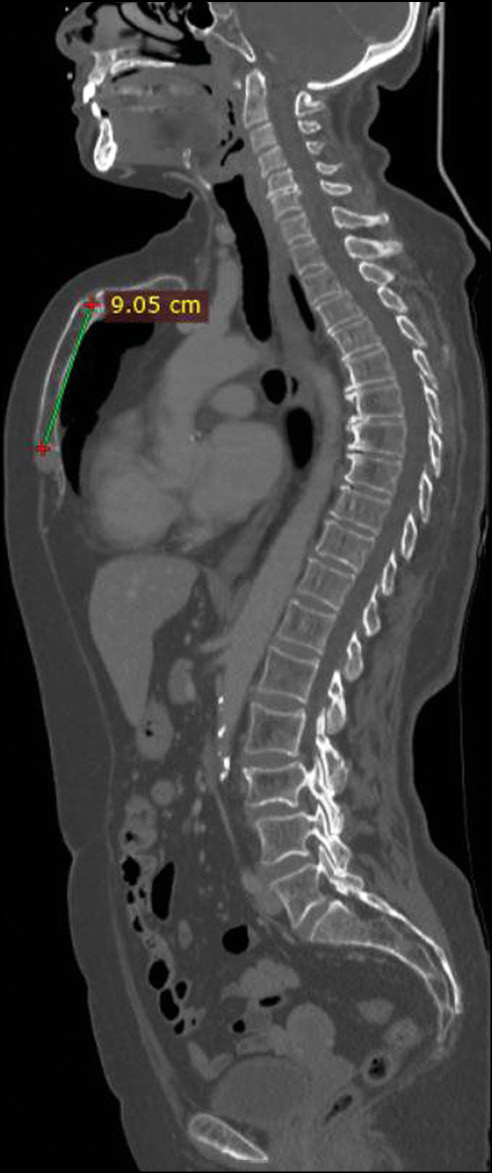

She underwent CT of the chest and abdomen with contrast enhancement, which showed the absence of metastatic lesions and any other respiratory tract disorders but revealed a chondromanubrial deformity with a dorsal-open angle of 130° and a sternum body length of 9 cm, which was not depressed in the lower third. Dorsal kyphosis was also present.

Fig 1. Sagittal whole body computed tomography scan showing an arching sternum and a chondromanubrial deformity with a dorsal-open angle of 130°.

Fig 2. Sagittal whole body computed tomography scan showing a sternum body length of 9 cm and dorsal kyphosis.